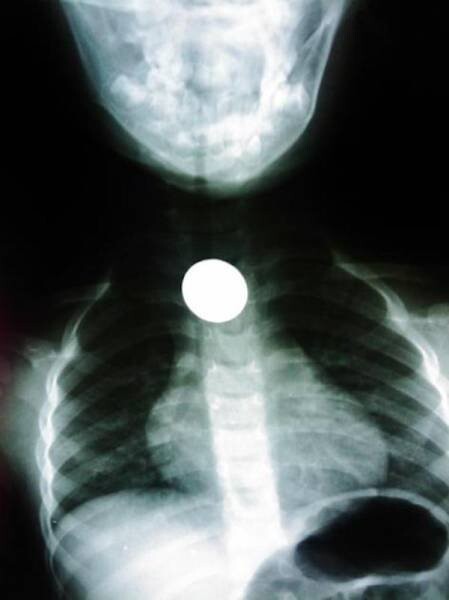

13. Монета